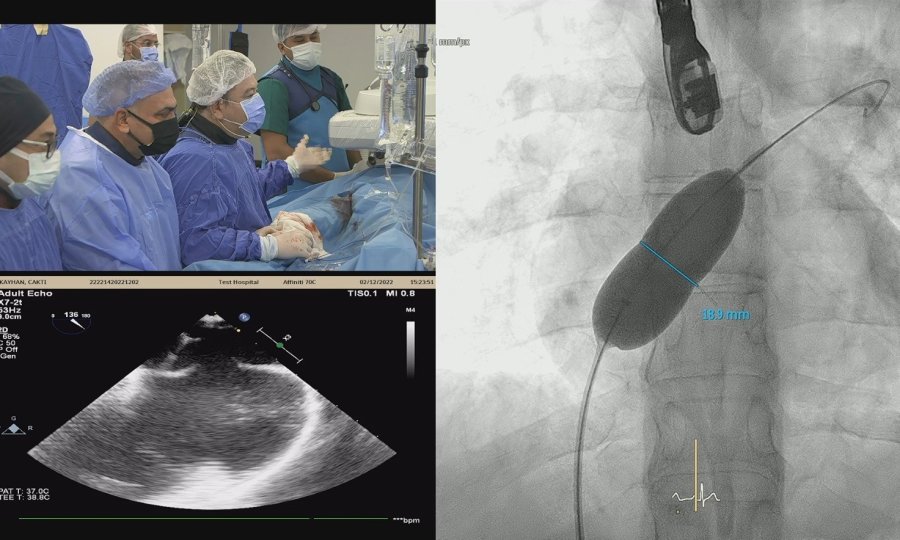

Türkiye Kalp ve Sağlık Vakfı tarafından 18'incisi düzenlenen Kardiyoloji ve Kardiyovasküler Cerrahide Yenilikler Kongresi, Akdeniz Üniversitesi ev sahipliğinde gerçekleşti. Kongrede 10 girişimsel kardiyoloji işlemi canlı yayımlandı.

Prof. Dr. Öztekin Oto ve Prof. Dr. Ali Oto tarafından kurulan Türkiye Kalp ve Sağlık Vakfı tarafından 18'incisi düzenlenen "Kardiyoloji ve Kardiyovasküler Cerrahide Yenilikler Kongresi", 1-4 Aralık tarihleri arasında Antalya Belek'te gerçekleştirildi. Kongre çerçevesinde Akdeniz Üniversitesi Hastanesi Tıp Fakültesi Kardiyoloji Bölümü Anjiyo Laboratuvarı'nda 10 kompleks girişimsel kardiyoloji işlemi yapıldı. Kongrenin ikinci günü 6, üçüncü günü 4 olmak üzere toplam 10 girişimsel kardiyoloji vakası başarıyla gerçekleşti. Birinci gün Amsterdam ile ortak bağlantı yapıldı. Japonya'dan Yoshihisa Kinoshita, Almanya'dan Kambis Mashayekhi, Türkiye'den Prof. Dr. Ömer Göktekin, Hollanda'dan Alexander Nap, Yunanistan'dan George Sianos gibi dünyaca tanınmış girişimsel kardiyologlar, kendi laboratuvarlarında yaptıkları girişimsel vakaları canlı olarak sundular. Bu canlı yayınlar Amsterdam'da ve Antalya Belek'te kongre katılımcıları tarafından canlı olarak izlendi.

Kongreye Patrick Peirer, Joe Coselli, Joe Bavaria gibi dünyaca ünlü kalp damar cerrahları da katıldı. Kongre hakkında bilgi veren Tıp Fakültesi Öğretim Üyesi Prof. Dr. Umuttan Doğan, "Akdeniz Üniversitesi Tıp Fakültesi Kardiyoloji Bölümü olarak Türkiye Kalp ve Sağlık Vakfı tarafından 18'incisi düzenlenen "Kardiyoloji ve Kardiyovasküler Cerrahide Yenilikler Kongresi'nin ikinci ve üçüncü gününde kardiyoloji ile ilgili kompleks vakaların yapıldığı operasyonlara ev sahipliği yaptık. Anjiyo Laboratuvarımızda canlı yayında kendi branşında hem dünyaca hem ulusal düzeyde tanınmış kardiyolog ve kardiyovasküler cerrah meslektaşlarımızla tartışarak yaptığımız vakaların tamamını başarıyla sonuçlandırmanın gururunu yaşıyoruz" diye konuştu.

Akdeniz Üniversitesi'ndeki canlı yayınlarda Prof. Dr. Ömer Göktekin, Prof. Dr. Nihat Kalay, Prof. Dr. Ertuğrul Okuyan, Prof. Dr. Engin Bozkurt gibi dünyaca tanınan kardiyologlar girişimsel işlemleri başarıyla gerçekleştirdiler. Kongrede kalp ve damar cerrahisi hastalıkları ile ilgili kompleks vakaların konuşulup tartışıldığını belirten Prof. Dr. Umuttan Doğan, "2 gün boyunca günlük hayatta karşılaşılan ya da nadir görülen kompleks vakaları alanında tanınmış meslektaşlarımızla canlı yayında eş zamanlı olarak bilimsel veriler ışığında tartıştık. Hastalarımızı tamamen bilimsel kurallara uyarak tedavi ettik. Akdeniz Üniversitesi olarak tüm hastalarımızı sağlıklarına kavuşturmanın sevincini yaşıyoruz" ifadelerini kullandı.